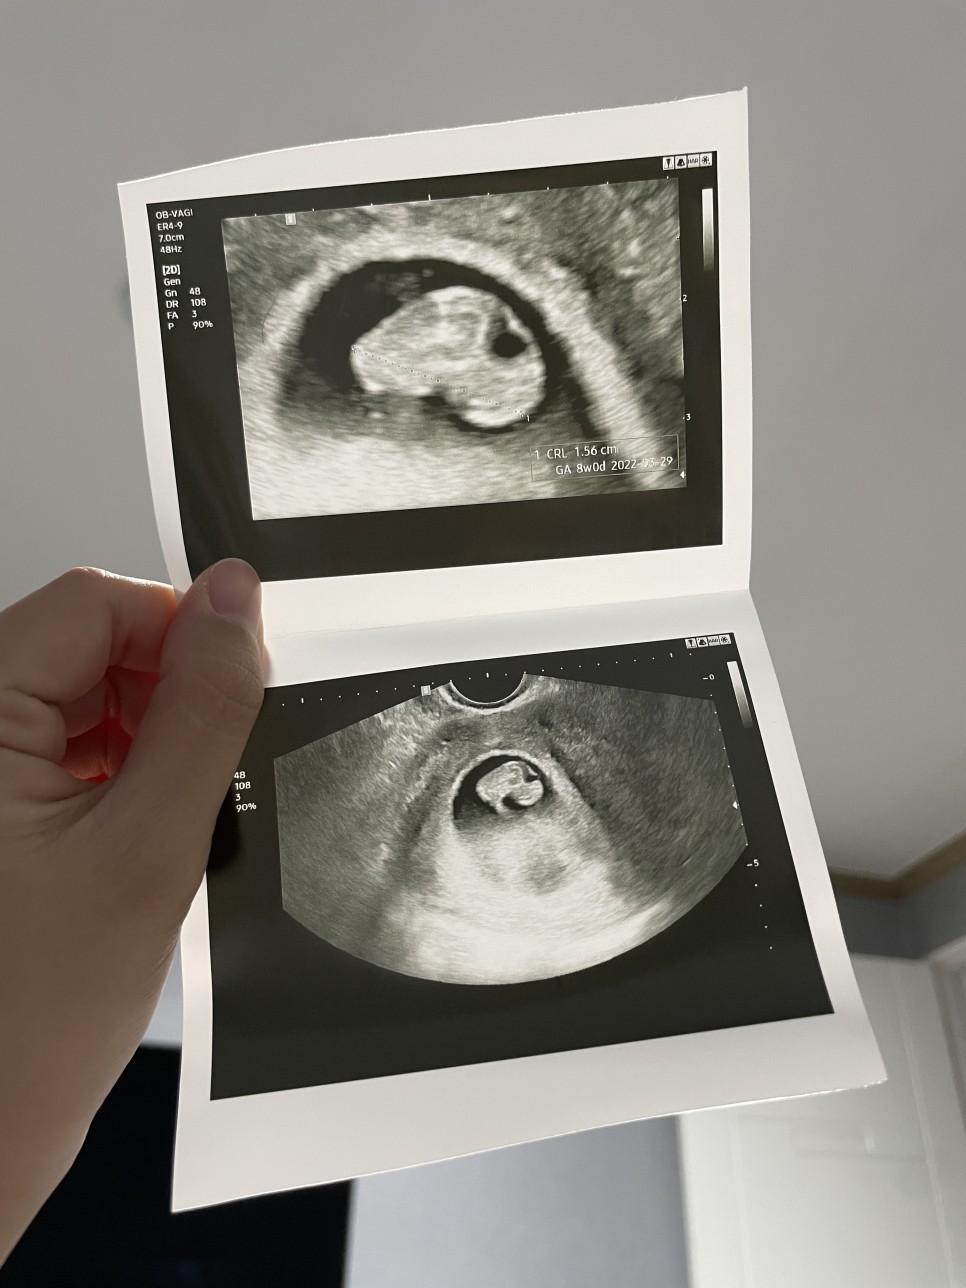

임신 8주 1일 기록

전 귀여운 젤리곰 기대했는데…8주차에 젤리곰을 볼 수 있다고 했잖아요 간호사선생님 ㅠㅠㅠㅠㅠㅠ

과장님 좋은데… 초음파는 좀 적당히 봐주는 경향이 있는것 같아TT 초음파 화질도 좋지않고…

그래도 8주 동안 주수대로 건강하게 성장하고 있다고 하셨기 때문에… 안심.